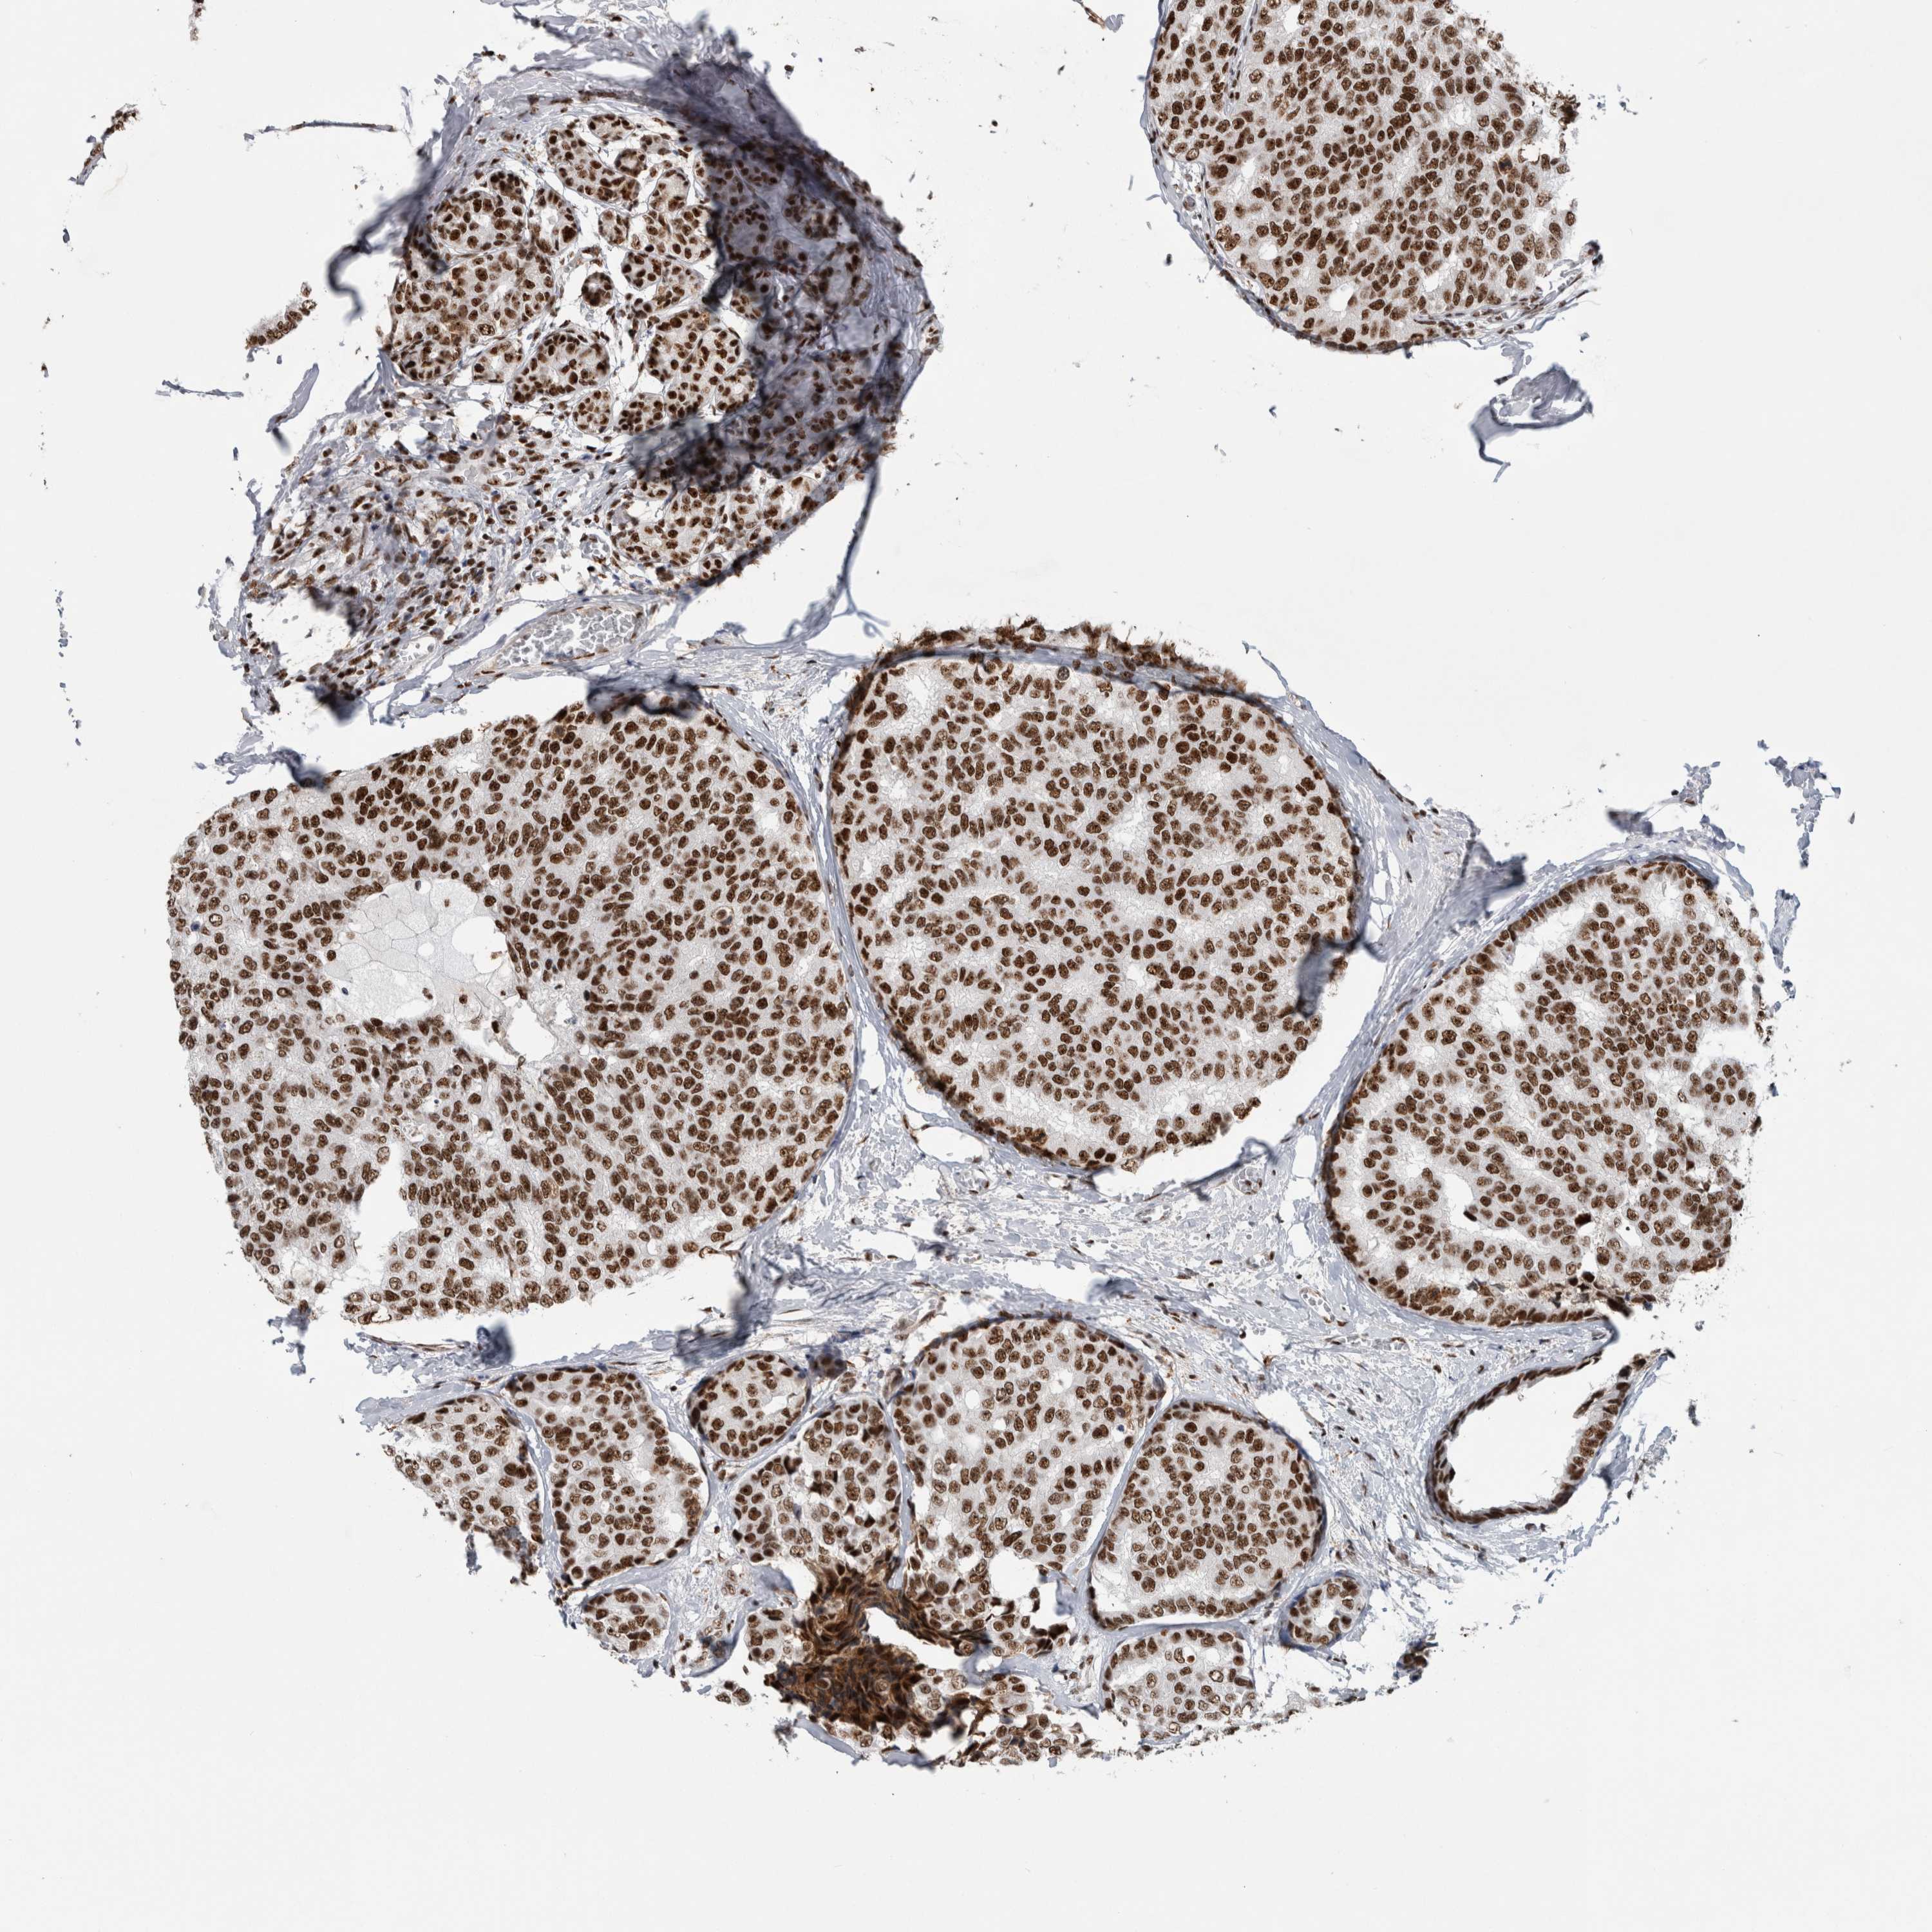

BRCA TCGA BRCA VALIDATION PROTEIN EXPRESSION